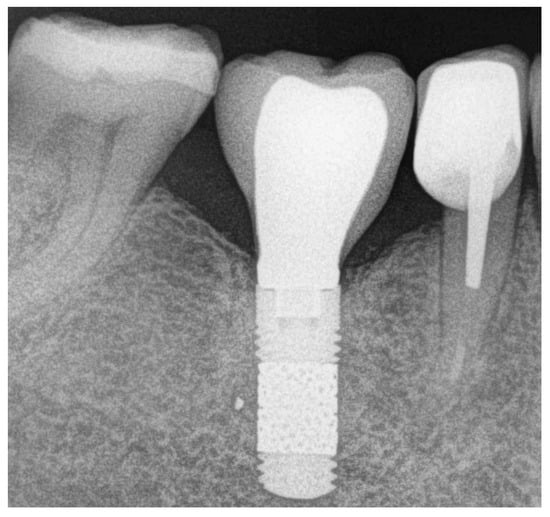

- Bone level changes were evaluated by comparing the measurements at baseline (on the day of prosthesis delivery) with those at follow-up visits. Measurements were obtained with an intraoral radiograph that depicted the vertical distance between the implant shoulder and the most coronal bone contact with the implant surface at mesial and distal sites. All the intraoral radiographs were taken using the parallel technique with an individual tray to ensure reproducibility. Measurements were always performed by the same experienced operator (S.B.) through the software ImageJ version 1.46 (National Institutes of Health, Bethesda, MD, USA), using the known TM implant diameter for calibration. The mesial and distal values were averaged to have a single value per implant.

| Mean value ± SD | −0.10 ± 0.16 | −0.21 ± 0.37 | −0.40 ± 0.38 | −0.51 ± 0.42 |

| Median (95% CI) | 0 (−0.19, −0.02) | 0 (−0.40, −0.01) | −0.3 (−0.60, −0.21) | −0.4 (−0.73, −0.29) |

| Mean change ± SD | −0.10 ± 0.29 | −0.30 ± 0.31 | −0.41 ± 0.38 | |